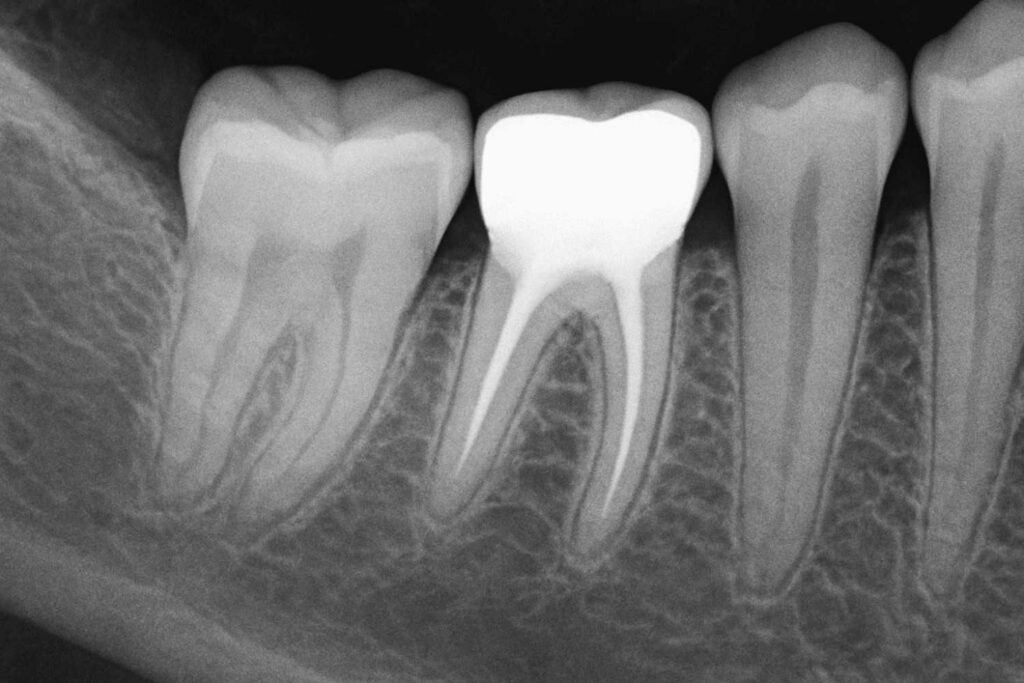

Radiopaque refers to any material or substance that appears white or light on X-ray images because it blocks or absorbs X-rays. This characteristic makes radiopaque substances highly visible on radiographic images—helping dentists identify, track, and monitor various structures in the mouth with high precision.

Define Radiopaque: In simple terms, radiopaque means “not allowing X-rays to pass through,” resulting in a bright, opaque appearance on radiographs.

This is different from radiolucent materials, which appear dark or black on X-rays because they allow X-rays to pass through. Understanding radiolucent vs radiopaque is key for interpreting dental X-rays accurately—helping to differentiate between healthy structures and potential problems.

Each of these materials shows up as a bright or white area on radiographs. This visibility helps dental professionals evaluate the positioning, integrity, and function of restorations or appliances with confidence.

This contrast allows dentists to identify decay, infection, bone loss, or the precise location of fillings and crowns. It’s essential for treatment planning.

Tooth enamel and jawbone are naturally radiopaque. Any drop in radiopacity can indicate decay, bone loss, or demineralization—prompting early intervention.

Understanding what radiopaque means can help patients interpret their X-rays. When your dentist points to a bright area on an image, that’s likely a filling, crown, or implant—and it’s supposed to be there!